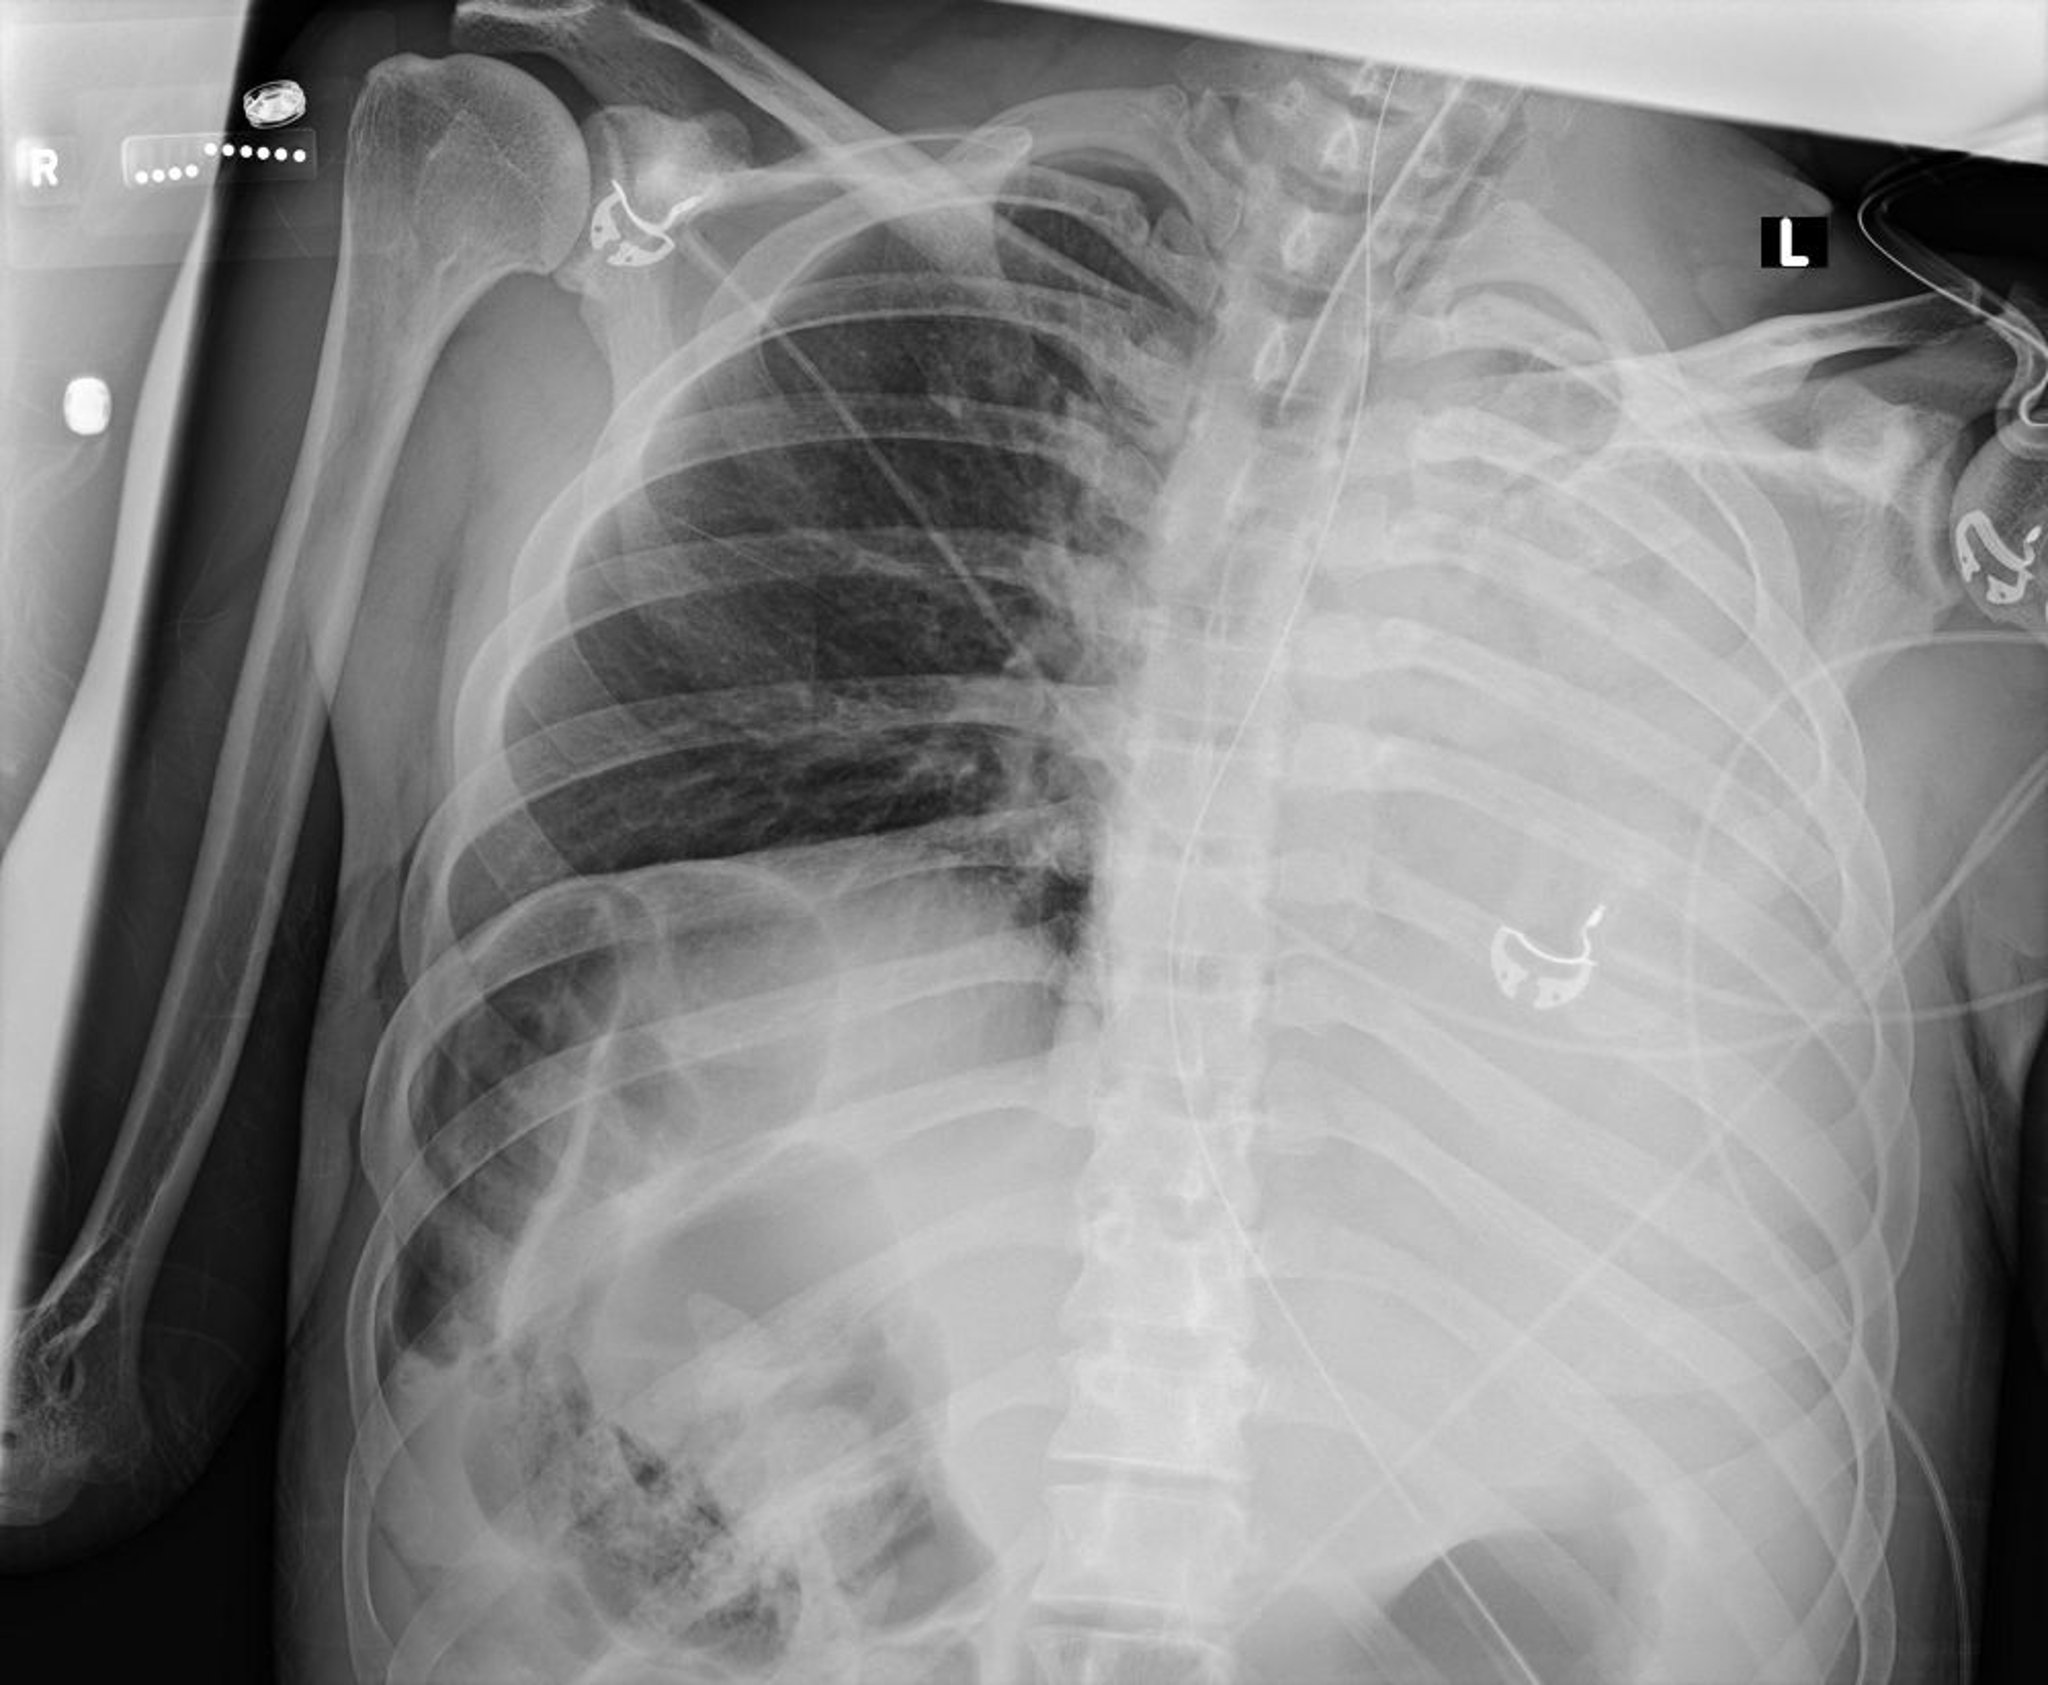

無気肺および左肺虚脱(X線)

この胸部X線写真は,粘液栓子による左肺の虚脱を示している。

Courtesy of Alexander S.Niven, MD